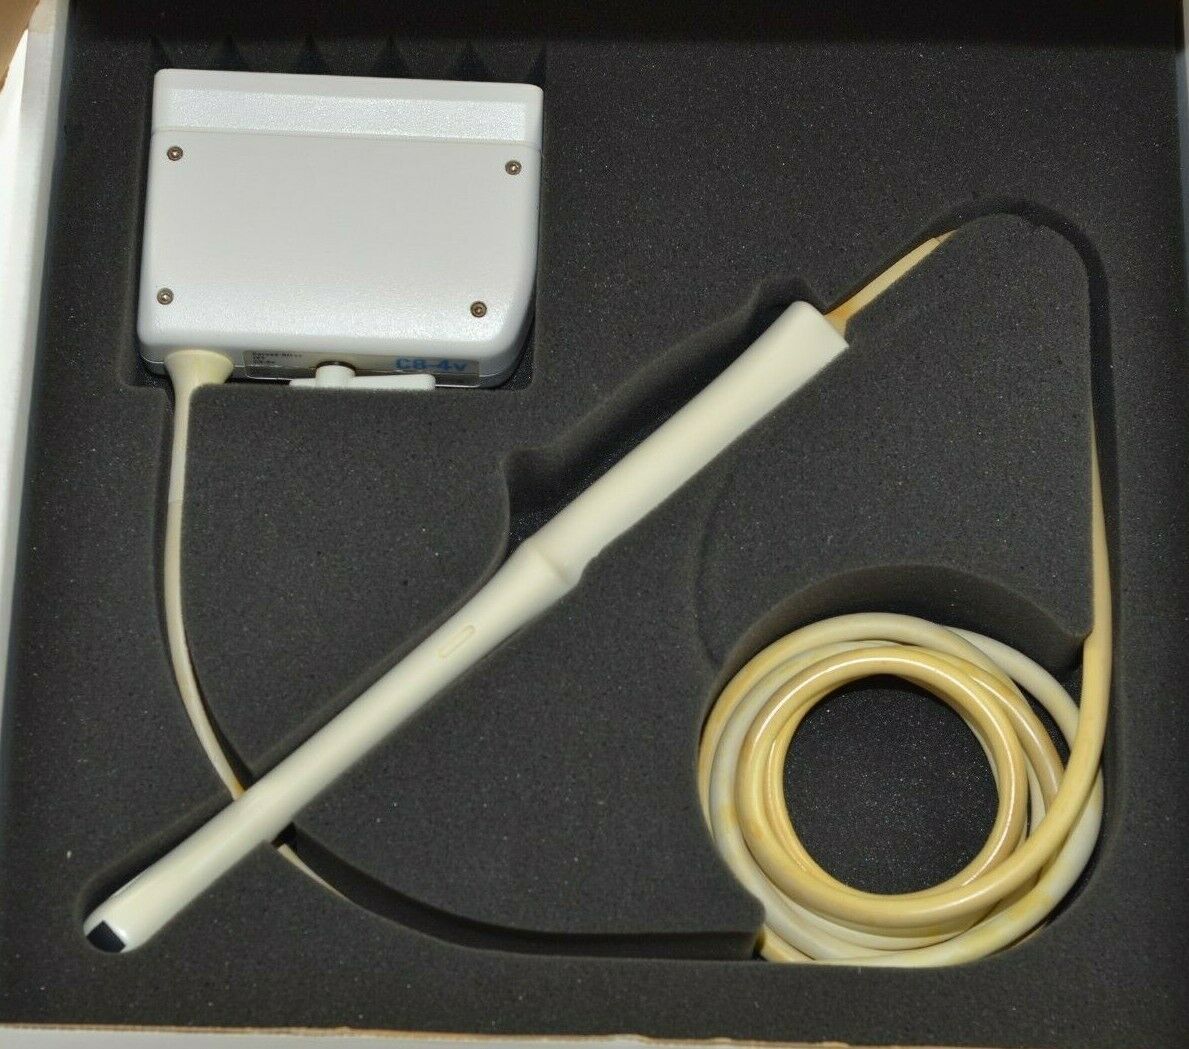

PHILIPS S12-4 ULTRASOUND TRANSDUCER PROBE

Sale price$ 4,305.00